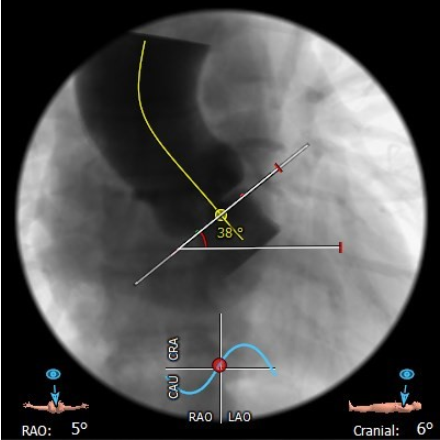

升主动脉可见增宽扩张,瓣环水平夹角38°

患者为TYPE0型二叶瓣,重度钙化,钙化主要分布在左侧瓣叶,瓣叶前后交界缘均可见局部融合,瓣环平面可见钙化,并延伸至左室流出道,左右冠开口高度均为14.3 mm,法式窦结构可,无明显冠脉阻塞风险。心脏角度约38°,左室不大,心肌肥厚,升主动脉可见增宽。